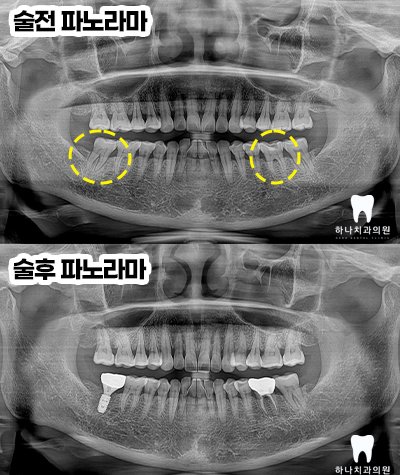

위 환.자분은 50대 여성분으로

오른쪽 아래 가장 안쪽 어금니가

밥을 먹을 때마다 깜짝 놀랄 정도로

통증이 느껴지신다고 하셨고

왼쪽 아래 치아는 깨졌다고

말씀해 주셨습니다.

양쪽 아래 어금니가 파절된 이유로

내원해 주셔서 두 치아의 진.단은

파절에 해당하지만 그 양상과

치료 방법이 달랐는데요.

오른쪽은 발치 후 임플란트 수복,

왼쪽은 신경치료 후 크라운 수복을

계획하였습니다.